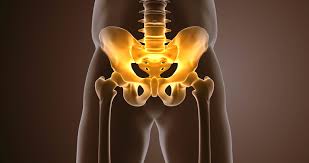

1. 고관절이란?

고관절은 골반과 대퇴골이 만나는 관절로, 인체에서 가장 크고 강한 관절 중 하나입니다. 이 관절은 공 모양의 대퇴골 두부와 그것을 감싸는 비구라는 구조로 구성되어 있으며, 몸의 체중을 지탱하고 걷기, 뛰기, 앉기, 서기 등의 동작을 가능하게 합니다. 고관절은 연골, 인대, 점액낭, 근육 등 다양한 조직이 유기적으로 작용하여 움직임과 안정성을 동시에 제공합니다.